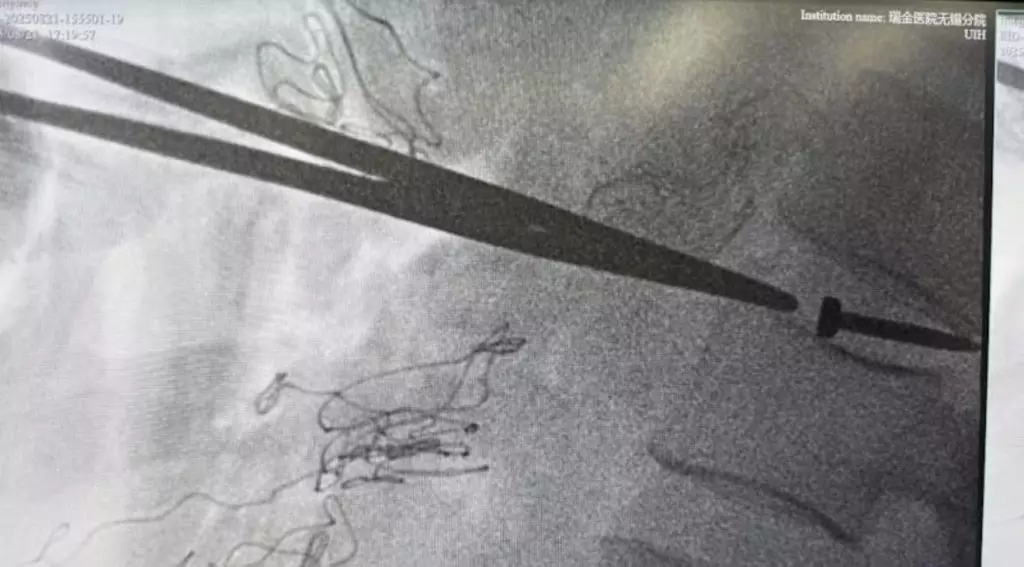

無錫裝修工遭釘槍射腹,送院揭3cm工程釘體內遊走了40CM貫穿腹腔內臟後卡腰椎間盤,醫生施3小時手術取出。

綜合內媒報導,江蘇無錫日前發生一起驚險安全事故,一名從事裝修工作的張師傅(化名)在施工期間不慎遭釘槍射中腹部,一枚長達3CM的金屬工程釘在張師傅的體內一路「遊走」40CM,最終卡在腰椎間盤內,所幸經醫生連續做3小時手術搶救後成功取出,暫時脫離險境。

醫院檢查顯示,這枚金屬釘自腹壁貫穿途經肝臟左葉、胃壁、結腸系膜、十二指腸及後腹膜,最終嵌入腰椎間盤。醫生坦言,若處理稍有不慎,隨時可能引發膽瘺及腸瘺等嚴重併發症,甚至可能危及生命。

醫療團隊立即為張師傅實施手術,歷時約3小時成功將帶有火藥尾部的工程釘取出。醫生強調,所幸金屬釘在穿過腹部時並未刺破大血管,且釘入位置剛好在椎間盤之間,未觸及脊髓,否則後果不堪設想。